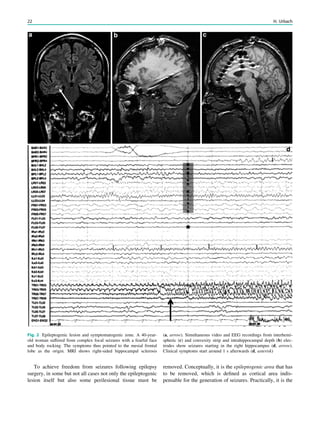

Fig. 2 Epileptogenic lesion and symptomatogenic zone. A 40-year-

old woman suffered from complex focal seizures with a fearful face

and body rocking. The symptoms thus pointed to the mesial frontal

lobe as the origin. MRI shows right-sided hippocampal sclerosis

(a, arrow). Simultaneous video and EEG recordings from interhemi-

spheric (c) and convexity strip and intrahippocampal depth (b) elec-

trodes show seizures starting in the right hippocampus (d, arrow).

Clinical symptoms start around 1 s afterwards (d, asterisk)

22 H. Urbach

seizure onset zone which it is intended to be removed, and

this is defined as the brain area in which ictal EEG activity

starts. The epileptogenic lesion usually shows at least some

overlap with the seizure onset zone and is therefore a good

indicator for its localization (Fig. 1).